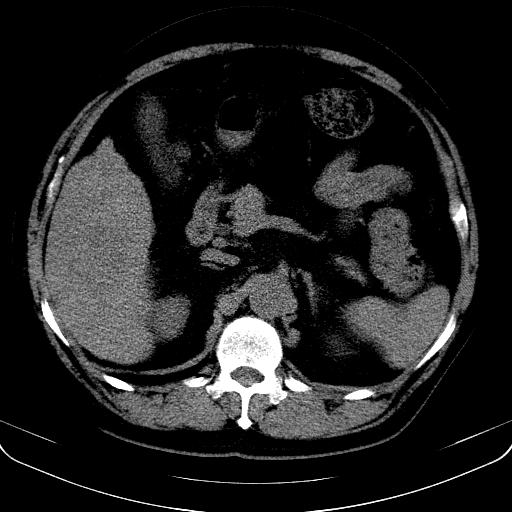

以下是引用jia119在2008-3-5 13:31:00的发言:[br]肝内多发片状低密度影,密度不均,我还是考虑肝ca可能,另肝内小囊肿,胆囊增大。

以下是引用形影不离在2008-3-5 12:18:00的发言:[br]肝硬化伴门脉高压征,肝内占位待排,增强再说.

以下是引用随光逐影在2008-3-5 21:11:00的发言:[br]肝硬化伴门脉高压(食管下段静脉曲张),肝癌不排除。建议:行ct增强扫描检查。

以下是引用同在2008-3-5 13:56:00的发言:[br]考虑肝癌可能性大,胆囊增大.